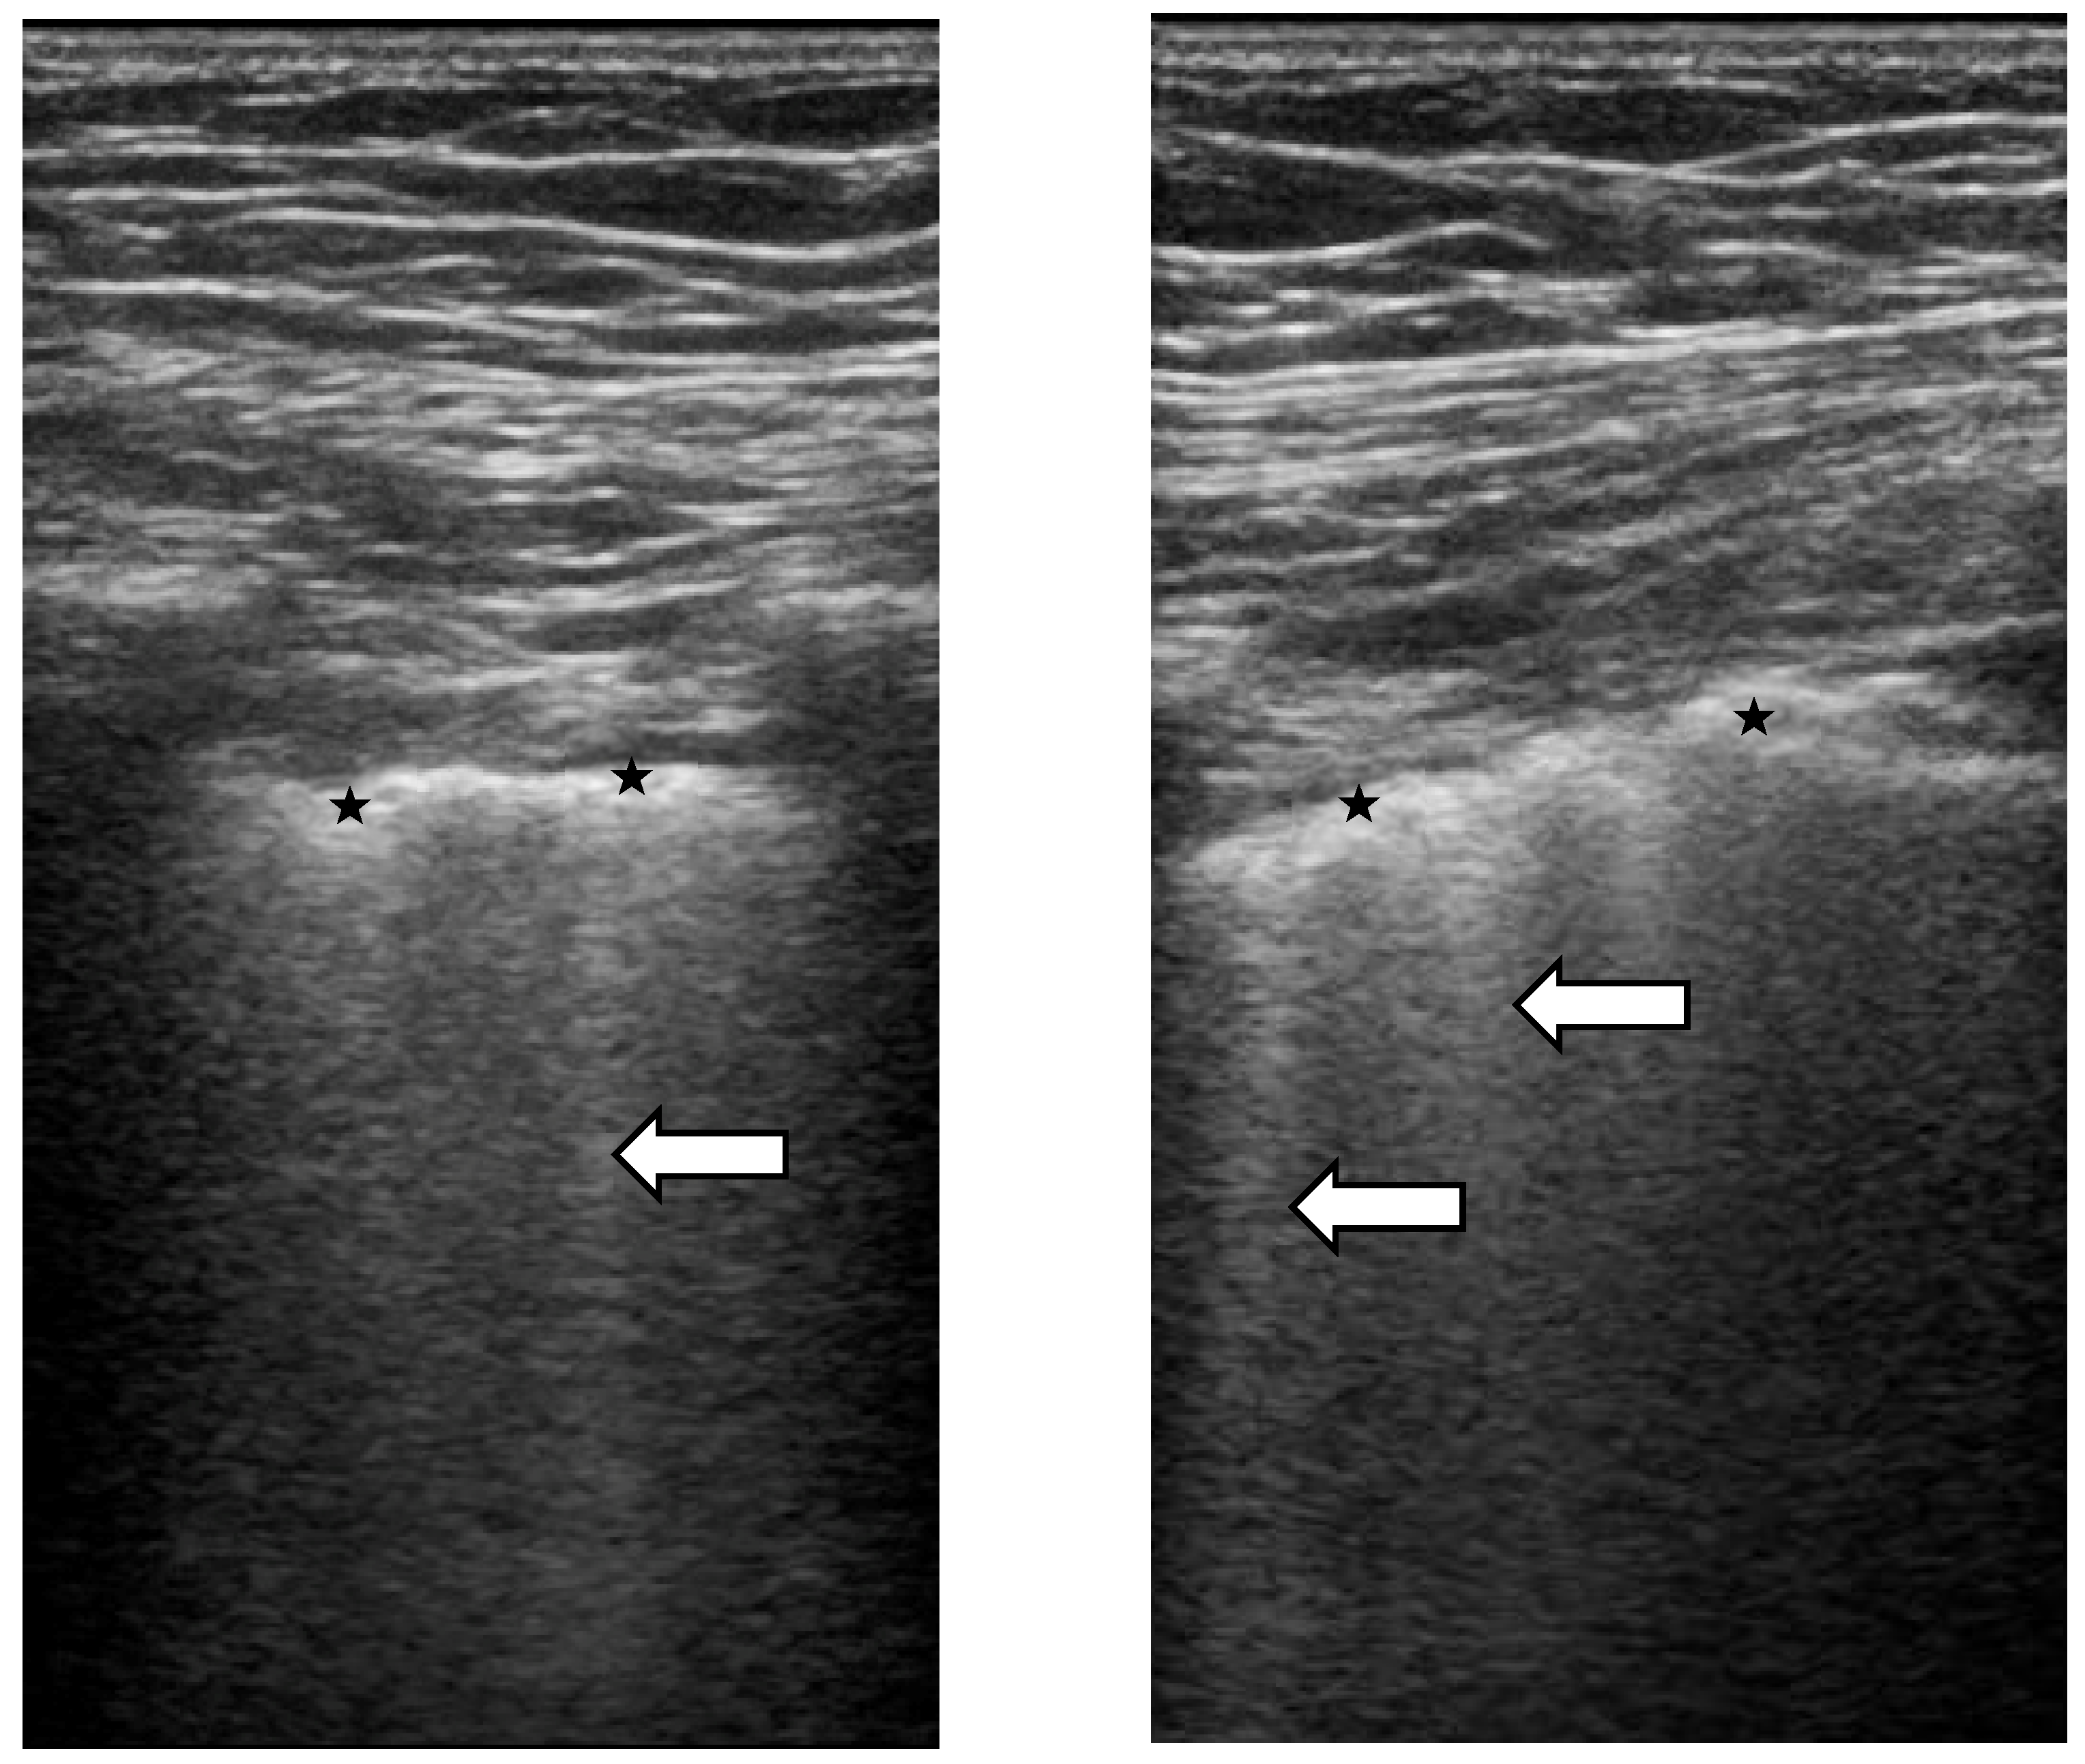

Lung Ultrasound in SSc-ILD: Qualitative Evaluation